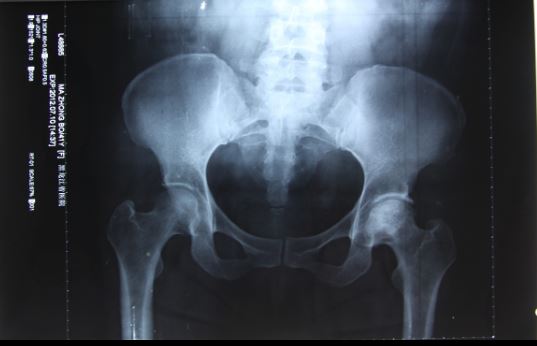

马忠波在北方股骨头坏死研究所的诊断

二零零零年三月,我到哈尔滨北方股骨头坏死研究所,我要取回我的病历和当时拍的CT片。我见到了曾给我看过病的研究所所长,见我走進来他们很震惊:你不是那个双侧股骨头坏死二期,在地上爬的那个患者吗?我说是啊。他惊讶的说:“你能走了?”我说:“你看我这不是走着来的吗”!张医生说:你走一个我看看?他忘了我是走着進去的。我就在屋里再给他走,我说我在家啥都能干了,我盖房子,打工什么都能干。他问我我就乐,他说搞的什么名堂快说说。张医生马上查找我的病历,一看只拿了一副药,就说:“你这绝不是用药的结果,快说说你是怎么好的?”

张医生商量着我再拍一个片子,看看我的腿到底啥样了,我说我好了还花那个闲钱?医生说不要钱。

我说那我也不拍,好象我炼法轮功还不信任这个功法似的。屋里的几个病人听说我是背着来的,现在好了,都想看看我这股骨头恢复得如何。那些人也说:孩子你拍一个我们也看看啥样了。在大家的劝说下我拍了片子。拍完这个片子医生把最初来看病拍的那个片子拿出来对照,发现两个片子一模一样,大夫说你这腿也没好啊?看你这股骨头还跟烂土豆似的。看片子我的股骨头并没有变化,但我人却行动自如了。医生让我走、蹲给他们看,在我身上看不出股骨头坏死患者的任何症状,要不是张医生和片子作证,在场的所有医生和患者怎么会相信呢?我说这法轮功可神奇了,看你信不信,你信就有人管你。我说那片子有没有股骨头关我啥事呀,我能走我不疼就行呗,那我自己不疼我不知道啊。医生也说:对对,你不疼就行呗,管他片子啥样呢。

在事实面前,一个医生说:“法轮功确实能治病。”另一个说:“可不,要不咋有那么多人炼。”医生说:“既然法轮功能出这样的奇迹,电视里说法轮功能治病是骗人的,你为什么不站出来说句公道话。”我说:“我会的!”在这里我顺理成章的把原来拍的片子拿了出来。

1、哈尔滨北方股骨头坏死研究所

一九九九年二月六日我第一次去哈尔滨北方股骨头坏死研究所,也是最后一次在医院检查确诊,见到的就是所长,他是一个很正直很讲医德的医生。二零零零年三月份我去过他们研究所重新拍了一个片子,片子所展现的还是股骨头坏死,但是那次我是一个完全恢复了健康的人去拜访他的,他也奇怪,怎么片子没有变化,人却不一样了。当时在他身边的一位年轻的医生说:这个病例可以记录在我们研究所的历史上了,所长却说:那不行,这个患者的病不是我们治好的,她是炼法轮功好的,和我们的治疗没有一点关系。

那篇文章,黑龙江省公安厅的人也看到了,去研究所调查我的事是否属实,张连喜医生实话实说的讲述了他亲眼见证了大法的神奇。医生把我的病例号(一九九九年三号)和二零零零年三月份拍的片子对比着讲给他们,两次拍片的结果都写着“双侧股骨头坏死”,但是炼法轮功后人是个健康的人了。省公安厅的人在那里也明白了事实真相,这件事就不了了之了。

二零一二年我又一次去了哈尔滨北方股骨头坏死研究所取片,那位所长又给我拍了个片子,结果仍然是股骨头坏死的症状。

2、黑龙江省医院

我修炼后三天就把那么严重的股骨头坏死炼好了,我去了修炼前曾经看过病的省医院拍片,医学影像科的医生张明磊给我拍完片子,那个大夫就在X光检查报告单上确诊的“股骨头坏死”后面打了个问号,在诊断书的下面写着:“观察”两个字。但是他写出病例了,盖的章。他给我做各种检查我都正常,走道,蹲起都行,他很纳闷。我就问他,问号是啥意思?他说:你是股骨头坏死。你这不是好了吗?我说我们家人让我花钱来拍片,就想看看片子怎么样。片子是啥样呢就给写啥样,家人只想要片子。你这问号是啥意思,我到底是不是股骨头坏死?他说:是,是股骨头坏死。但是你哪都不疼,你不都正常了吗?他也不明白是怎么回事。他对我提出的问号很后悔,大夫的名章已经盖上了没有办法再改变了,也只好那样了,他一再说:是股骨头坏死,是股骨头坏死。

二零一二年七月十号在黑龙江省医院检查股骨头坏死的诊断。